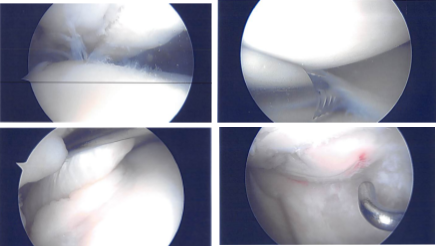

An Esmarch was applied, and tourniquet was raised to 325 mmHg. A lateral entry portal was made for the knee scope and the scope was entered. The patellofemoral joint was intact. The scope was moved to the medial compartment. Fraying of the medial meniscus was seen.

A medial entry portal was made using a spinal needle. The medial meniscus tear was excised using a straight biter and shaver. The scope was moved to the intercondylar notch where an ACL was intact. It was moved to the lateral femoral fraying of the medial margin of the lateral meniscus also.

The shaver and straight biters were used on the medial margin of lateral meniscus to a balanced margin. The scope was again moved to the patellofemoral joint where the fracture was seen and found to be displaced. The fracture was cleaned and an osteotome was used to release the fracture from the arthroscopic portal.

Intraoperative Arthroscopy Images

The arthroscope was inserted to check the reduction and found to be appropriate. There was some cartilage damage around the edge which was debrided. Hemostasis was achieved. Closure was performed in layers after the closure of the quadriceps tendon and the paratenon.